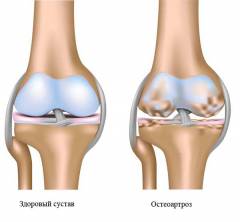

Деформирующий остеоартроз — дегенеративно-дистрофическое заболевание, затрагивающее хрящевую ткань суставов. Причинами остеоартроза могут быть травмы, воспаления или дисплазия. На начальном этапе изменения касаются синовиальной жидкости, питающей хрящ. Затем патологические изменения затрагивают и сустав. Пораженный сустав не выдерживает обычные нагрузки, что приводит к воспалению и боли. На второй стадии происходит разрушение хрящевой ткани и образование остеофитов, так как кость пытается перераспределить нагрузку. Третья стадия характеризуется выраженной деформацией суставных поверхностей, нестабильностью сустава и укорочением связок. В дальнейшем могут возникать патологические движения или ограничения активных движений (развиваются контрактуры).

Костно-хрящевые остеофиты образуются из-за деформации хрящевой ткани. Суставные поверхности обычно покрыты хрящом, который снижает трение между костями. Однако при постоянных нагрузках или воспалительных и дегенеративных заболеваниях хрящ может истончаться и разрушаться. В ответ на механические нагрузки кость начинает разрастаться, образуя остеофиты, которые увеличивают площадь суставной поверхности и равномерно распределяют нагрузку.

Остеофиты чаще всего возникают в крупных суставах, таких как коленный и тазобедренный, где нагрузка максимальна.